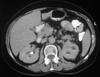

Case presentation: We present a case of a 68-year-old woman who underwent a computed tomography scan of the abdomen in the work-up for recently diagnosed hypertension. A non-enhancing left renal sinus mass was detected extending to the para-aortic space. The initial diagnosis was that of a tumor of the collecting system. Nephro-ureterectomy was performed and the pathology results revealed changes of chronic pyelonephritis.